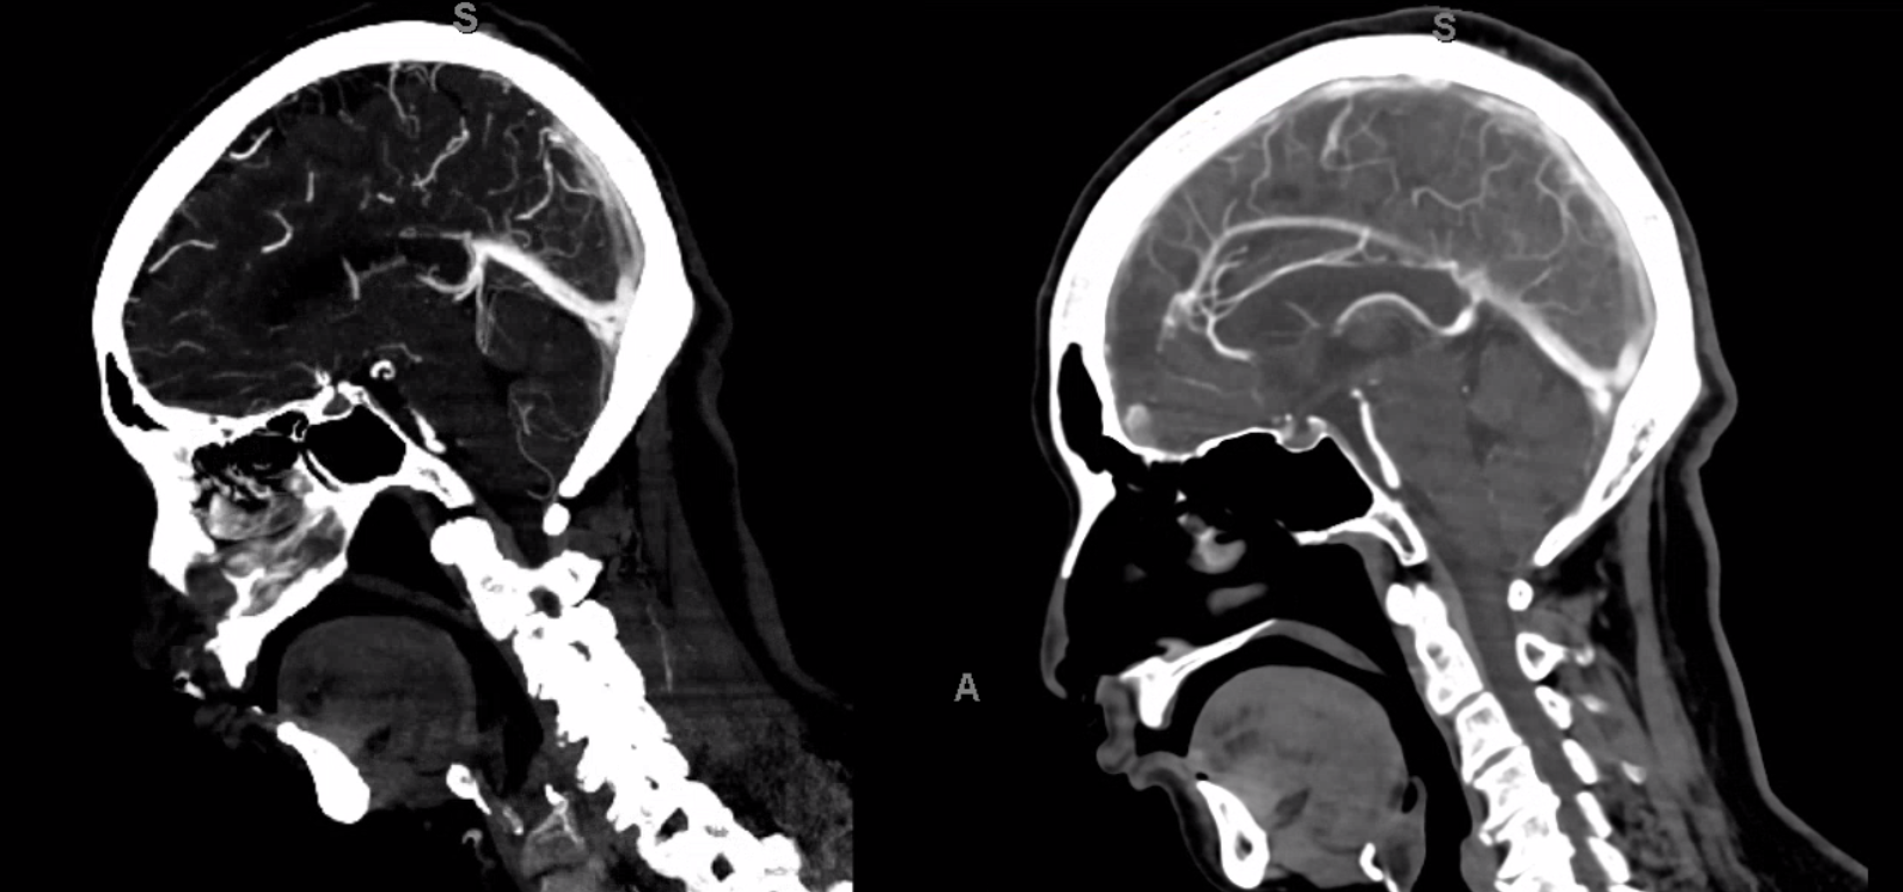

Below are some volumetric images, before we dive in

Pause movies to scroll thru individual frames

A poorly timed, venous phase CTA shows small caliber of sagital sinus

A poorly timed, venous phase CTA shows small caliber of sagital sinus